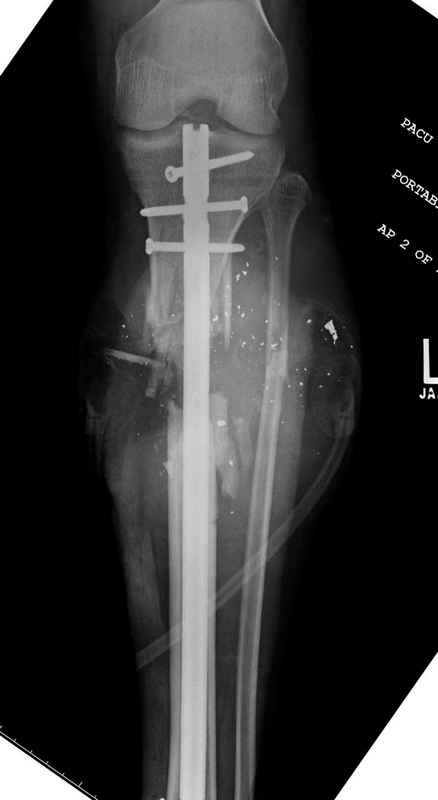

Здесь представлен больной 27 лет с ранениями, включая огнестрельный перелом большеберцовой кости.

14.08.09 повторная Irrigation&Debridment (чувстительственность из раны негативная) со сменой фиксации на медуллярный гвоздь и вакуумирование VAC

Имя     : 11 gsw tibila post IM nail.jpg

Тип     : image/jpeg

Размер  : 24313 байтов

Описание: отсутствует

Url     : http://weborto.net:8080/pipermail/ortho/attachments/20090831/f744a2dd/attachment-0023.jpg